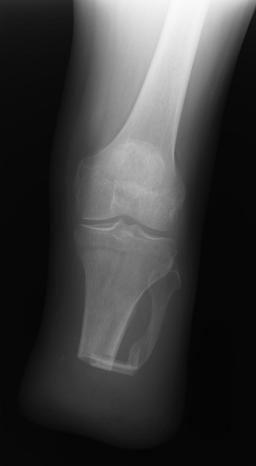

X-Rays and scans of the damaged right & left legs plus the pelvis

These x-rays were taken just after the accident. Some of the bones on the right leg have already been pushed back into the leg. The CT

scans show various views of the ankles and pelvis prior to any corrective surgery. Fibula bracing is clear in some of the images as well as

bracing that was used to secure the "open book" pelvis. In some of the last images it is apparent that the upper part of Liam’s left fibula is

broken. Liam was told that the pain he felt was most likely a muscle cramp. Nothing was done to repair this break and you will see in further

x-rays that the bone shifted and later fused in such a way as to add to the reduction of Liam’s leg length. The last photo shows the stint

used to block any potential blood clots from moving up.